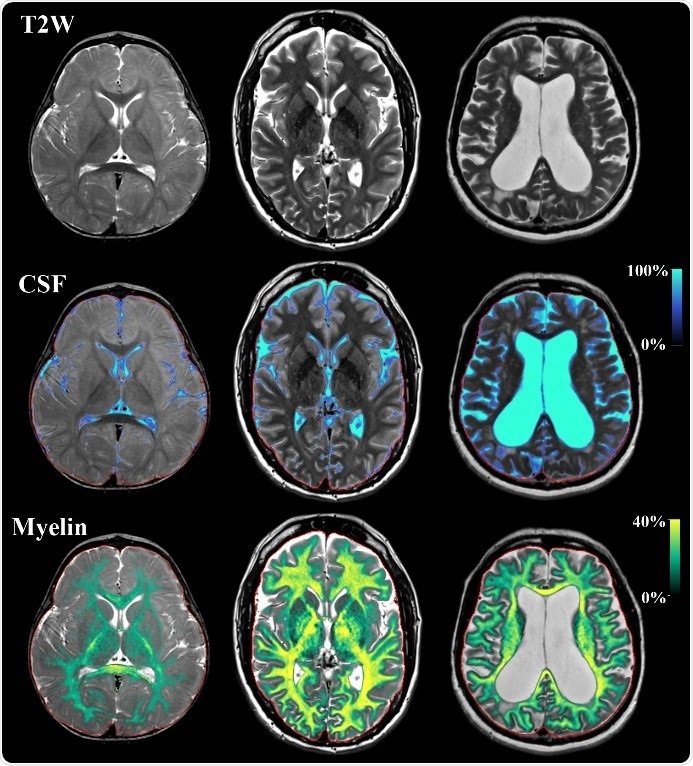

Example of SyMRI imaging on three subjects with the age of 1 year, 43 years and 73 years old. Displayed are synthetic T2-weighted images of an axial slice of the brain. On the same slice a tissue segmentation is performed of cerebrospinal fluid (CSF) and of myelin. Using this map, radiologists can follow signal changes, brain volume and the state of myelination. The acquisition takes 5 minutes for full coverage of the brain.

The approach has recently become commercially available under the name SyMRI and is manufactured by SyntheticMR in Sweden. The advantage of SyMRI is that the scan time of the sequence is only around 5 minutes and the data not only provides myelin maps, but can also synthesize conventional T1W, T2W and FLAIR images. Postprocessing is performed in seconds. The sequence is available on all major vendor platforms.

By using these parameters, tissue can further be classified to provide clinically relevant information. One such an example is the detection of myelin in the brain. Myelin rapidly evolves during childhood. However, disease and aging may cause degradation, which impairs the signal transmission in the nerves and may lead to atrophy and brain dysfunction. Accurate in-vivo myelin measurements would therefore be valuable for the diagnosis and follow-up of developmental disorders and neurodegenerative diseases.